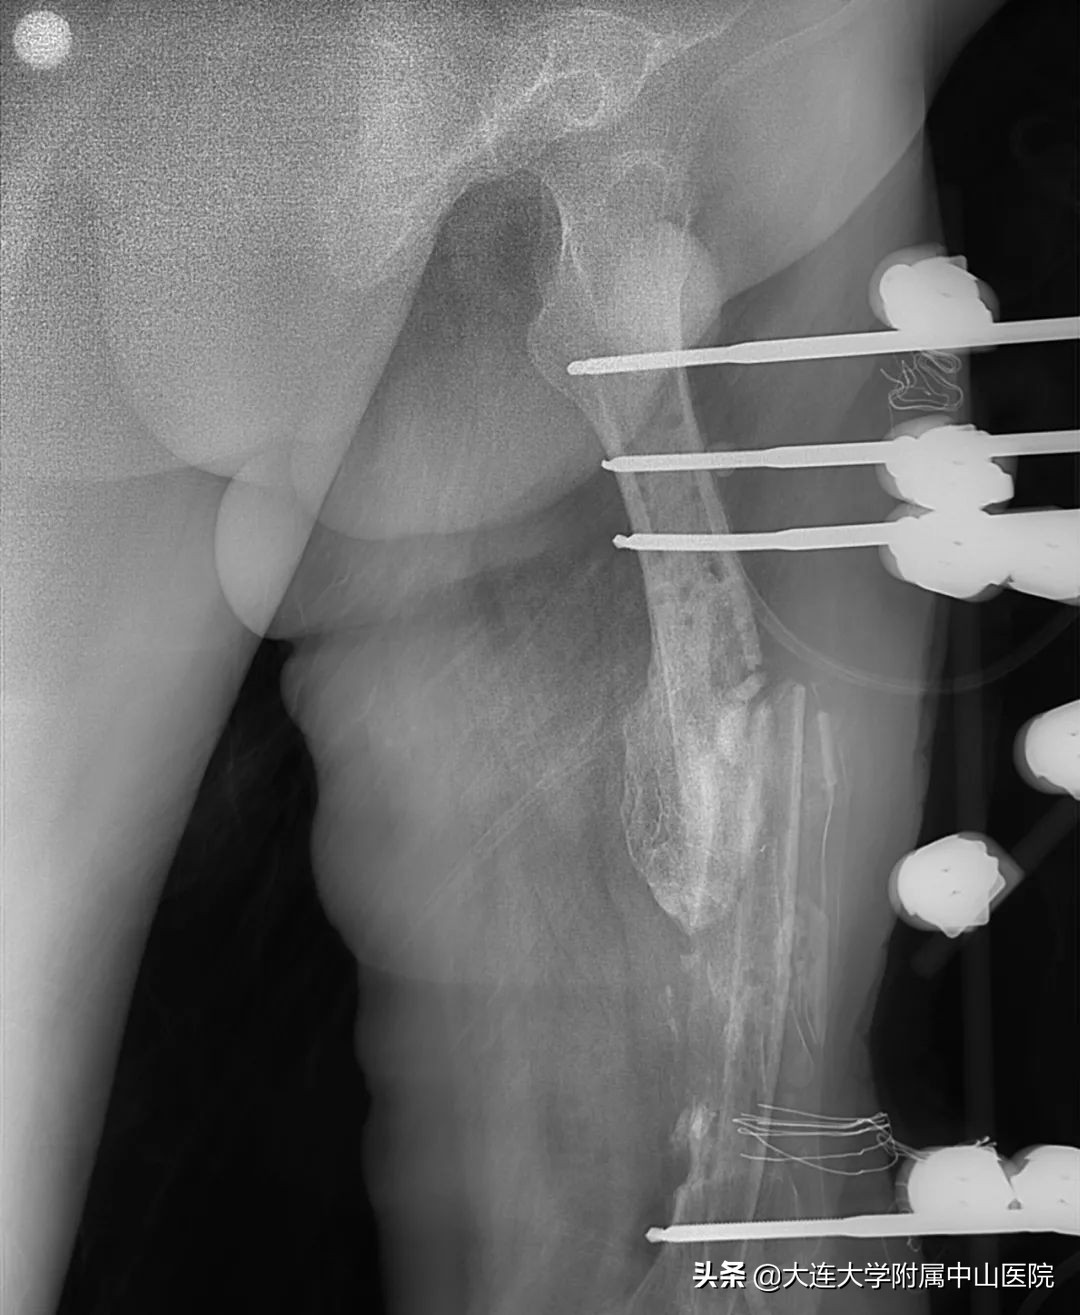

就在患者要放弃治疗,准备截肢的时候,偶然得知大连大学附属中山医院造船分部擅长于骨创治疗,就抱着试试看的态度来到了造船分部。接诊的秦松主任与患者做了深入沟通,打消了患者的悲观情绪,为患者制定了详尽的手术方案,在患者的积极配合与秦主任团队的共同努力下,前后历时一年,经过了病灶清除术、抗生素骨水泥占位术、腓骨移植术等数次前卫医疗技术手段,通过传统及现代治疗技术相结合,不仅控制住感染,还将长达18厘米长的骨缺损全部修复,患者终于保住了大腿,又重新站立起来了,回归了正常生活。